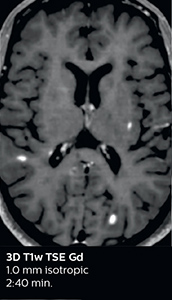

Fast MS protocol with optional sequences

The abbreviated MS protocol for brain is only around 9 minutes, so in case of suspected multiple sclerosis, one or two more advanced sequences may be added, such as PSIR (phase sensitive inversion recovery) or susceptibility-weighted sequences to help us make more confident diagnoses in these inflammatory cases.

In this example, the optional 3D multishot susceptibility weighted sequence with 0.6 mm isotropic voxels is 2 lesions with a central vein sign (arrows) and one lesion with a phase-rim sign (arrowhead). The total scan time, including SmartBrain and axial PD/T2 3mm, is 11:10 min. and is 18:30 min. with the optional 3D PSIR and 3D SWI multishot included.

“In multiple sclerosis patients, we increasingly include a multishot susceptibility sequence [3] in our routine cases, thanks to the shorter scan times. Our abbreviated MS protocol for brain is around 8 to 9 minutes, so we can ask for one or two additional sequences to visualize the central veins, or to get an additional contrast to better depict posterior fossa lesions. In cases of white matter lesions of unknown significance on FLAIR images, for example when we see high signal hyperintensities in the brain, we can add on more advanced sequences such as PSIR (phase sensitive inversion recovery) or susceptibility-weighted sequences to help us in distinguishing between MS and nonspecific or vascular abnormalities in these inflammatory cases.”